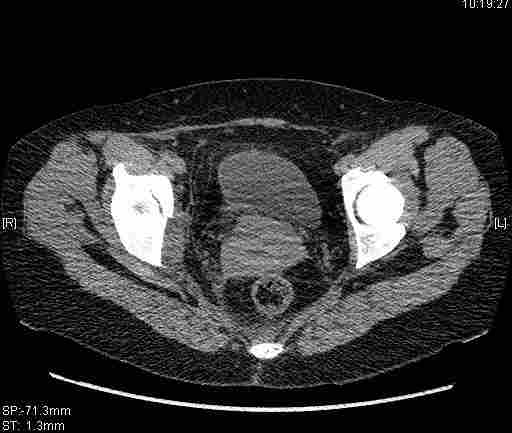

[Ortho] [1/2] Re: Т-образный перелом вертлужной впадины

Удалось сегодня вывести пациентку в соседнюю больницу, где есть кт.

Срезы сделаны  только горизонтальные.